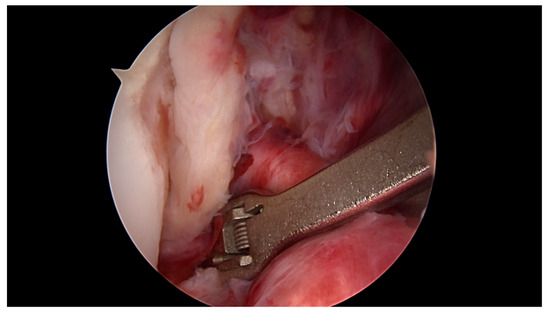

Primary Proximal ACL Repair: A Biomechanical Evaluation of Different Arthroscopic Suture Configurations

Purpose: Several suture techniques have been described in the past for direct ACL repair with poor healing capacity and a high re-rupture rate. Therefore, we investigated a refixation technique for acute primary proximal ACL repair. The purpose of this study is to [...] Read more.

Purpose: Several suture techniques have been described in the past for direct ACL repair with poor healing capacity and a high re-rupture rate. Therefore, we investigated a refixation technique for acute primary proximal ACL repair. The purpose of this study is to compare the biomechanical properties of different suture configurations using a knotless anchor. Methods: In this study, 35 fresh-frozen porcine knees underwent proximal ACL refixation. First, in 10 porcine femora, the biomechanical properties of the knotless anchor, without the ligament attached, were tested. Then, three different suture configurations were evaluated to reattach the remaining ACL. Using a material testing machine, the structural properties were evaluated for cyclic loading followed by loading to failure. Results: The ultimate failure load of the knotless anchor was 198, 76 N ± 23, 4 N significantly higher than all of the tested ACL suture configurations. Comparing the different configurations, the modified Kessler–Bunnell suture showed significant superior ultimate failure load, with 81, 2 N ± 15, 6 N compared to the twofold and single sutures (50, 5 N ± 14 N and 37, 5 ± 3, 8 N). In cyclic loading, there was no significant difference noted for the different configurations in terms of stiffness and elongation. Conclusions: The results of this in vitro study show that when performing ACL suture using a knotless anchor, a modified Kessler–Bunnell suture provides superior biomechanical properties than a single and a twofold suture. Within this construct, no failure at the bone–anchor interface was seen. Clinical relevance: Since primary suture repair techniques of ACL tears have been abandoned because of inconsistent results, ACL reconstruction remains the gold standard of treating ACL tears. However, with the latest improvements in surgical techniques, instrumentation, hardware and imaging, primary ACL suture repair might be a treatment option for a select group of patients. By establishing an arthroscopic technique in which proximal ACL avulsion can be reattached, the original ACL can be preserved by using a knotless anchor and a threefold suture configuration. Nevertheless, this technique provides an inferior ultimate failure load compared to graft techniques, so a careful rehabilitation program must be followed if using this technique in vivo. Full article

(This article belongs to the Special Issue Treatment of Anterior Cruciate Ligament Injuries)

Show Figures